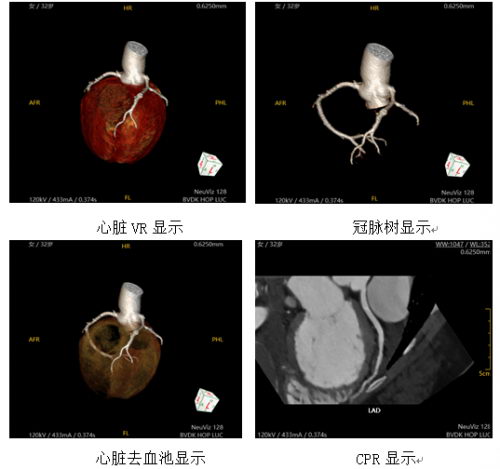

在众人的期待目光中,合力医院用NeuViz 128 精睿CT完成了装机后的首例冠状动脉CTA扫描。主治医生随即根据影像结果,排除了患者的心肌梗死诊断,并展开下一步的精准救治。

在信中,合力医院说道,“NeuViz 128精睿CT的临床功能十分全面,尤其是在紧急关头,东软医疗CT临床专家展示出了出色的专业水平,理收获院方的感谢信。在本例患者心率达到100次/分钟以上,且无法配合屏气及上举双臂的情况下,这台设备依然能够得到满足临床诊断的冠脉CTA图像,院方表示高度认可”。